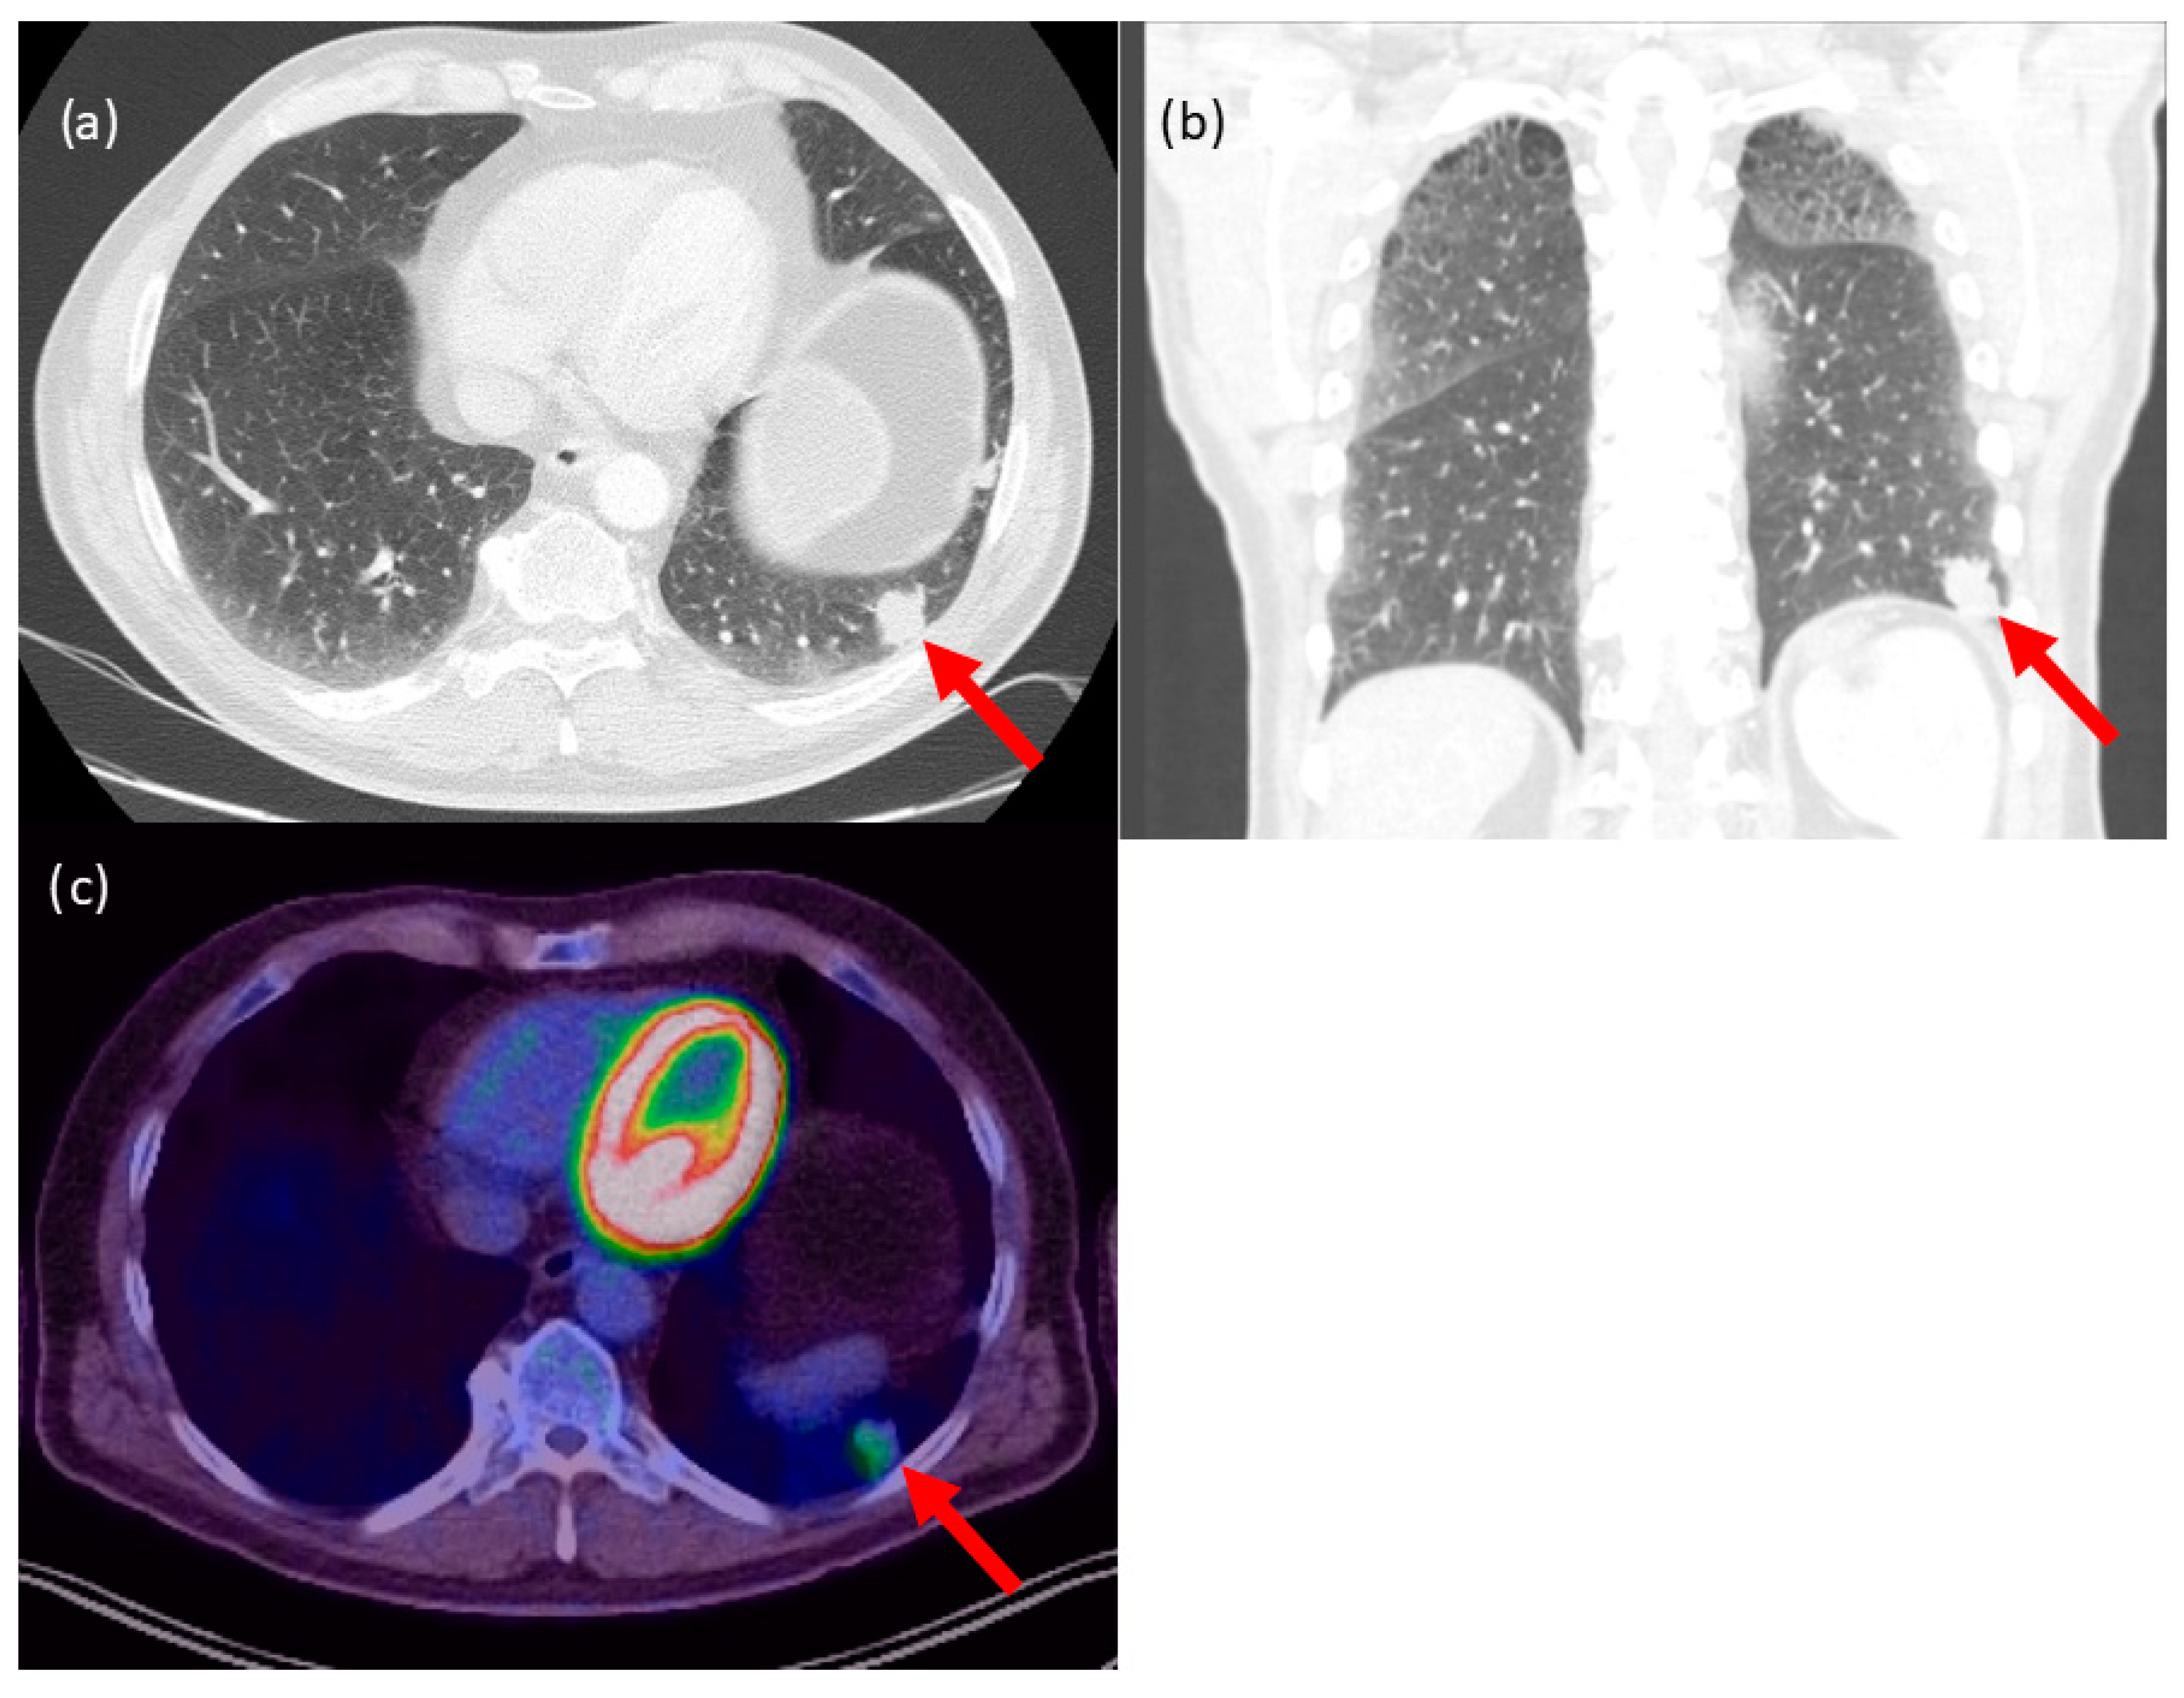

3.6. Case 1

3.7. Case 2